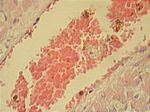

Myokarditis diphterica, HE